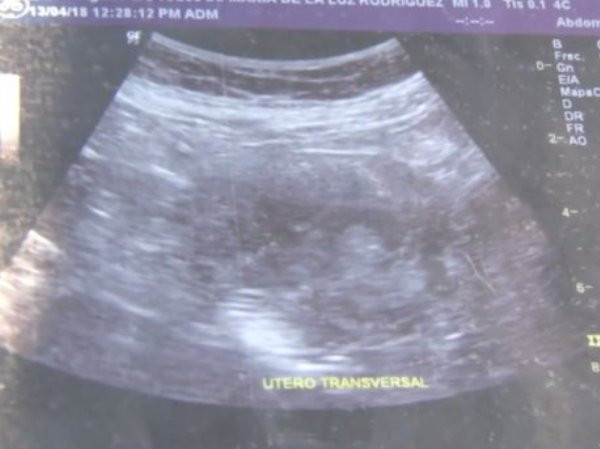

"Các bác sĩ bảo tôi đó là con gái. Các anh nhìn xem, khuôn mặt nhỏ bé này", cụ Maria đưa ra hình chụp siêu âm có bào thai trong đó và chỉ cho phóng viên xem.

Hình ảnh siêu âm đứa bé trong bụng bà Maria de la Luz